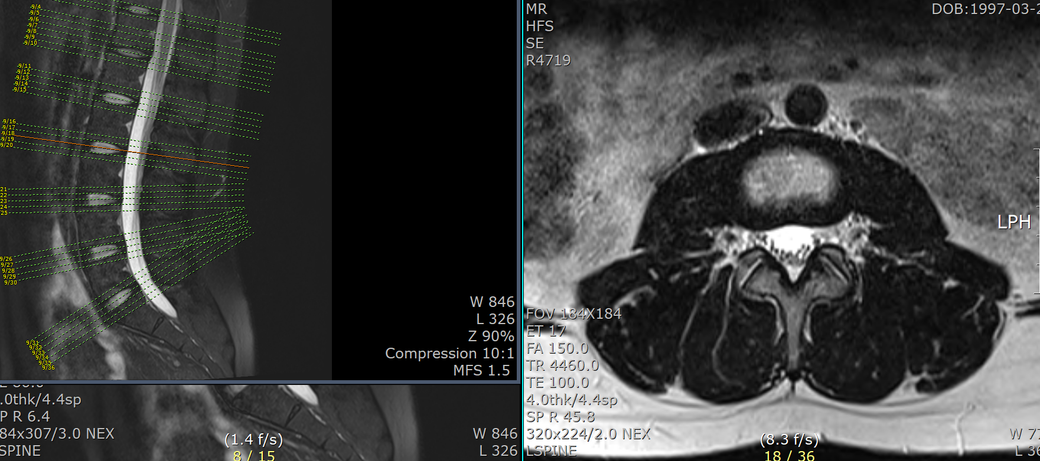

mri 판독 결과 남깁니다..

T12-L1 level에서 disc가 뒤쪽 Lt. central aspect로 protrusion되어 있고 mild한 dural sac indentation을 주고 있음.

그 외 disc level과 neural foramen에서 definite한 abnormality는 보이지 않음.

• 4번 째 사진

아래 사진에 있는 부위가 아마 T12/L1 사이에 디스크가 살짝 뒤로 빠져있다는 부위이실겁니다.

우선은 이 디스크 내장증으로 인한 연관통으로 보고 요추전만 자세를 잘 실천해보시는게 가장 우선 필요한 조치이겠습니다.

수술을 주로 다루는 신경외과, 정형외과 선생님들의 경우에 심한 디스크탈출 및 신경뿌리를 누르는 신경뿌리병증이 생길만한 병변만 통증을 유발한다고 보시기 때문에 문제될만한 병변이 없다고 이야기 하셨을텐데 저렇게 작게 찢어진 디스크 때문에도 충분히 통증이 생길 수 있습니다. 물론 찢어진 디스크의 위치에 비해 통증이 밑에 있는 편이시지만 이게 불가능한건 아닙니다. 디스크 내장증이라고 하며 이럴때는 요추전만 자세가 가장 중요합니다.

피부가 찢어지면 봉합을 하듯이 찢어진 부위가 아물도록 상처를 오므려놓는게 필요한데 이게 바로 요추전만 자세의 유지입니다.

허리를 하루에 한번도 안굽힌다고 생각하고 생활해보시기 바랍니다.

머리도 서서 샤워하면서 감으셔야합니다. 아마 1달 이내에 통증이 많이 줄어드는걸 느끼실 수 있을겁니다.